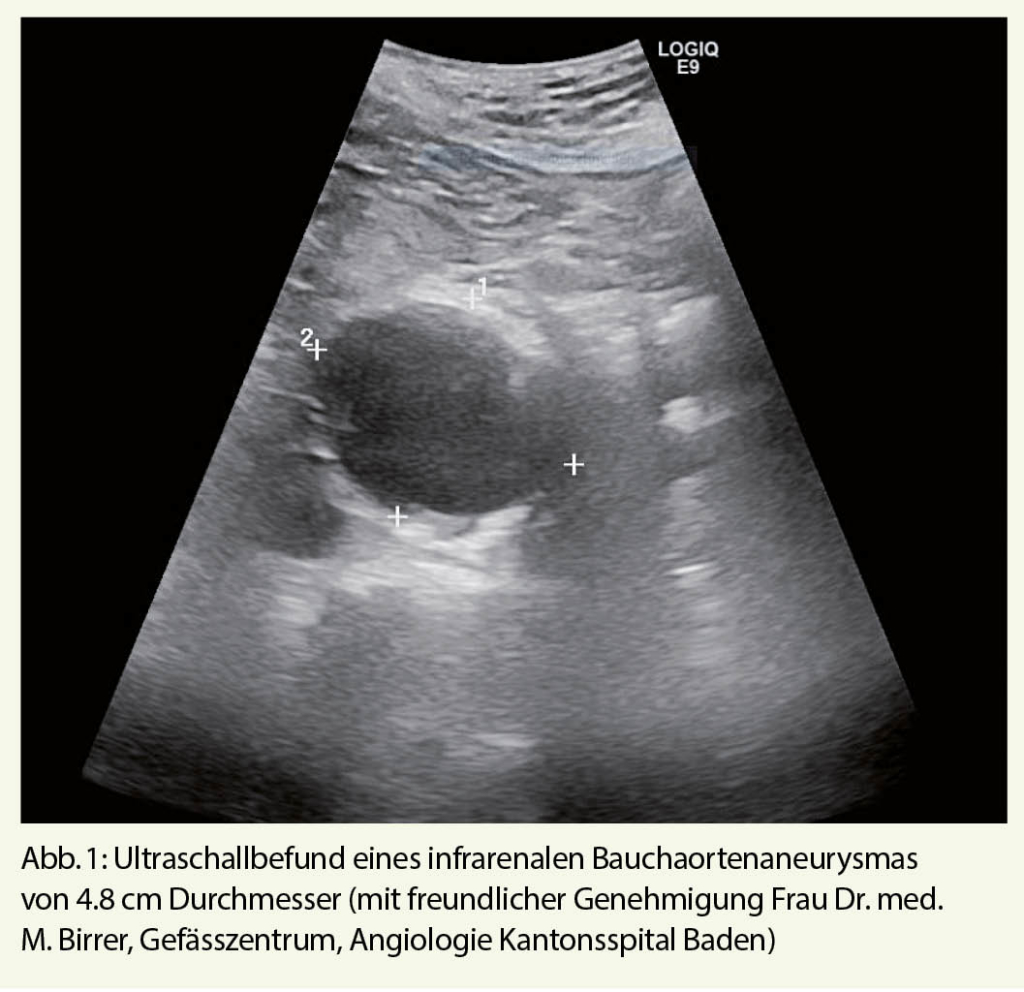

Nun, das Screening für das BAA erfüllt diese Kriterien in idealer Weise. Vier grosse randomisierte Studien haben sich in der Vergangenheit der Frage gewidmet, ob das Screening für das BAA die Aneurysma-spezifische, und die Gesamtmortalität bei der Zielgruppe, Männern über 65 Jahren, verringern kann (6-9). Zwei dieser Studien wurden in Grossbritannien, eine in Dänemark und eine weitere in Australien durchgeführt. Nur eine dieser vier Studien hat sich derselben Frage bei Frauen gewidmet (10). Als diagnostische Methode kam jeweils der Ultraschall zur Anwendung, welcher in 98.5% der Fälle eine genaue Diagnose stellen kann (Abb. 1) (11). Die Metaanalyse der Cochrane Bibliothek konnte nach einer Nachsorge von drei bis fünf Jahren eine deutliche Reduktion um zirka 40% der Aneurysma-spezifischen Mortalität bei Männern in den Screening-Gruppen ausmachen (Odds Radio 0.95, 95% CI 0.85-1.07)(12). Dies gilt ebenfalls, wenn auch nur in geringem Ausmass, für die Gesamtmortalität, welche in den Screening-Gruppen auch nach langer Nachsorge verringert werden konnte (Risk ratio 0.987, 95% CI 0.975-0.99, p=0.03) (13). Auf der Basis der Grossbritannischen MASS (Multicentre Aneurysm Screening Study)-Studiendaten kann man folgendes Model erstellen: In der Annahme dass 80% der aufgebotenen Patienten zum Screening erscheinen, und dass die postoperative Mortalität der elektiven Aneurysma-Operation 5% beträgt, was für heutige Verhältnisse eher hoch ist, muss man 240 Männer einladen, um einen frühzeitigen Aneurysma-bedingten Tod über 10 Jahre zu vermeiden (Number needed to Screen = 240) (14). Dies wurde von mehreren nationalen Gesundheitssystemen als kosteneffektiv angesehen (z. B. U. S. Preventive Services Task Force, NICE Guidelines).